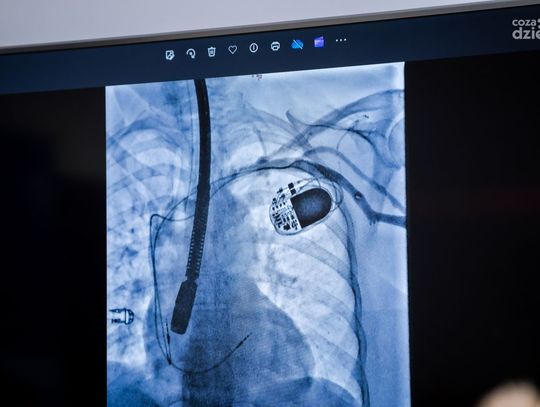

Stymulator serca w formie kapsułki - konferencja (zdjęcia)

stymulator serca